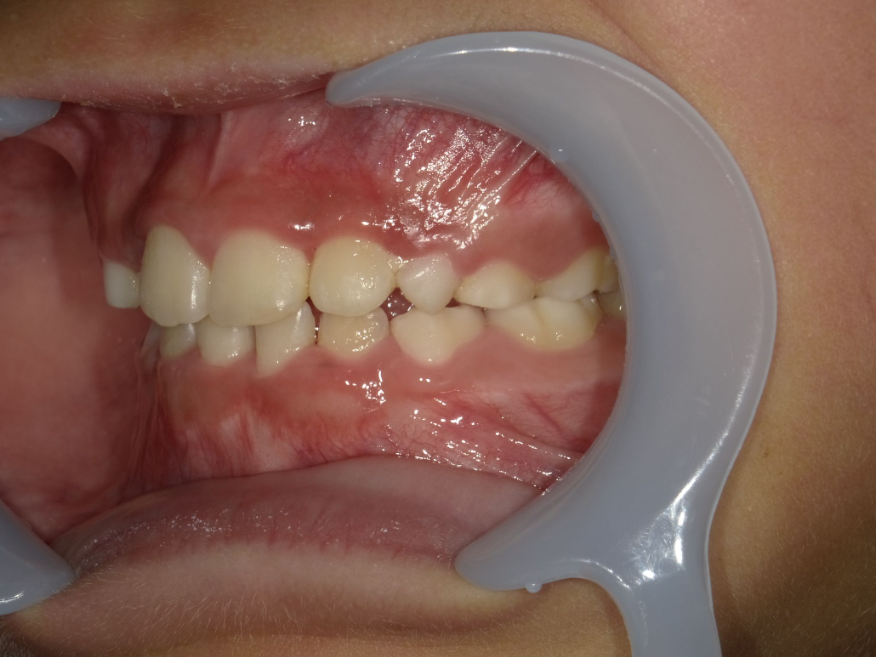

右横

| 治療内容 | インビザライン・ファースト |

| 治療詳細 | スペース不足や交叉咬合を整えるために、歯の表面にアタッチメント(白い突起)をつけ、治療を行いました。 |

| 患者情報 | 9歳 男性 予防矯正から移行 |

| 主訴 | 永久歯は生えそろう十分なスペースがない 一部分だけかみ合わせが反対 |